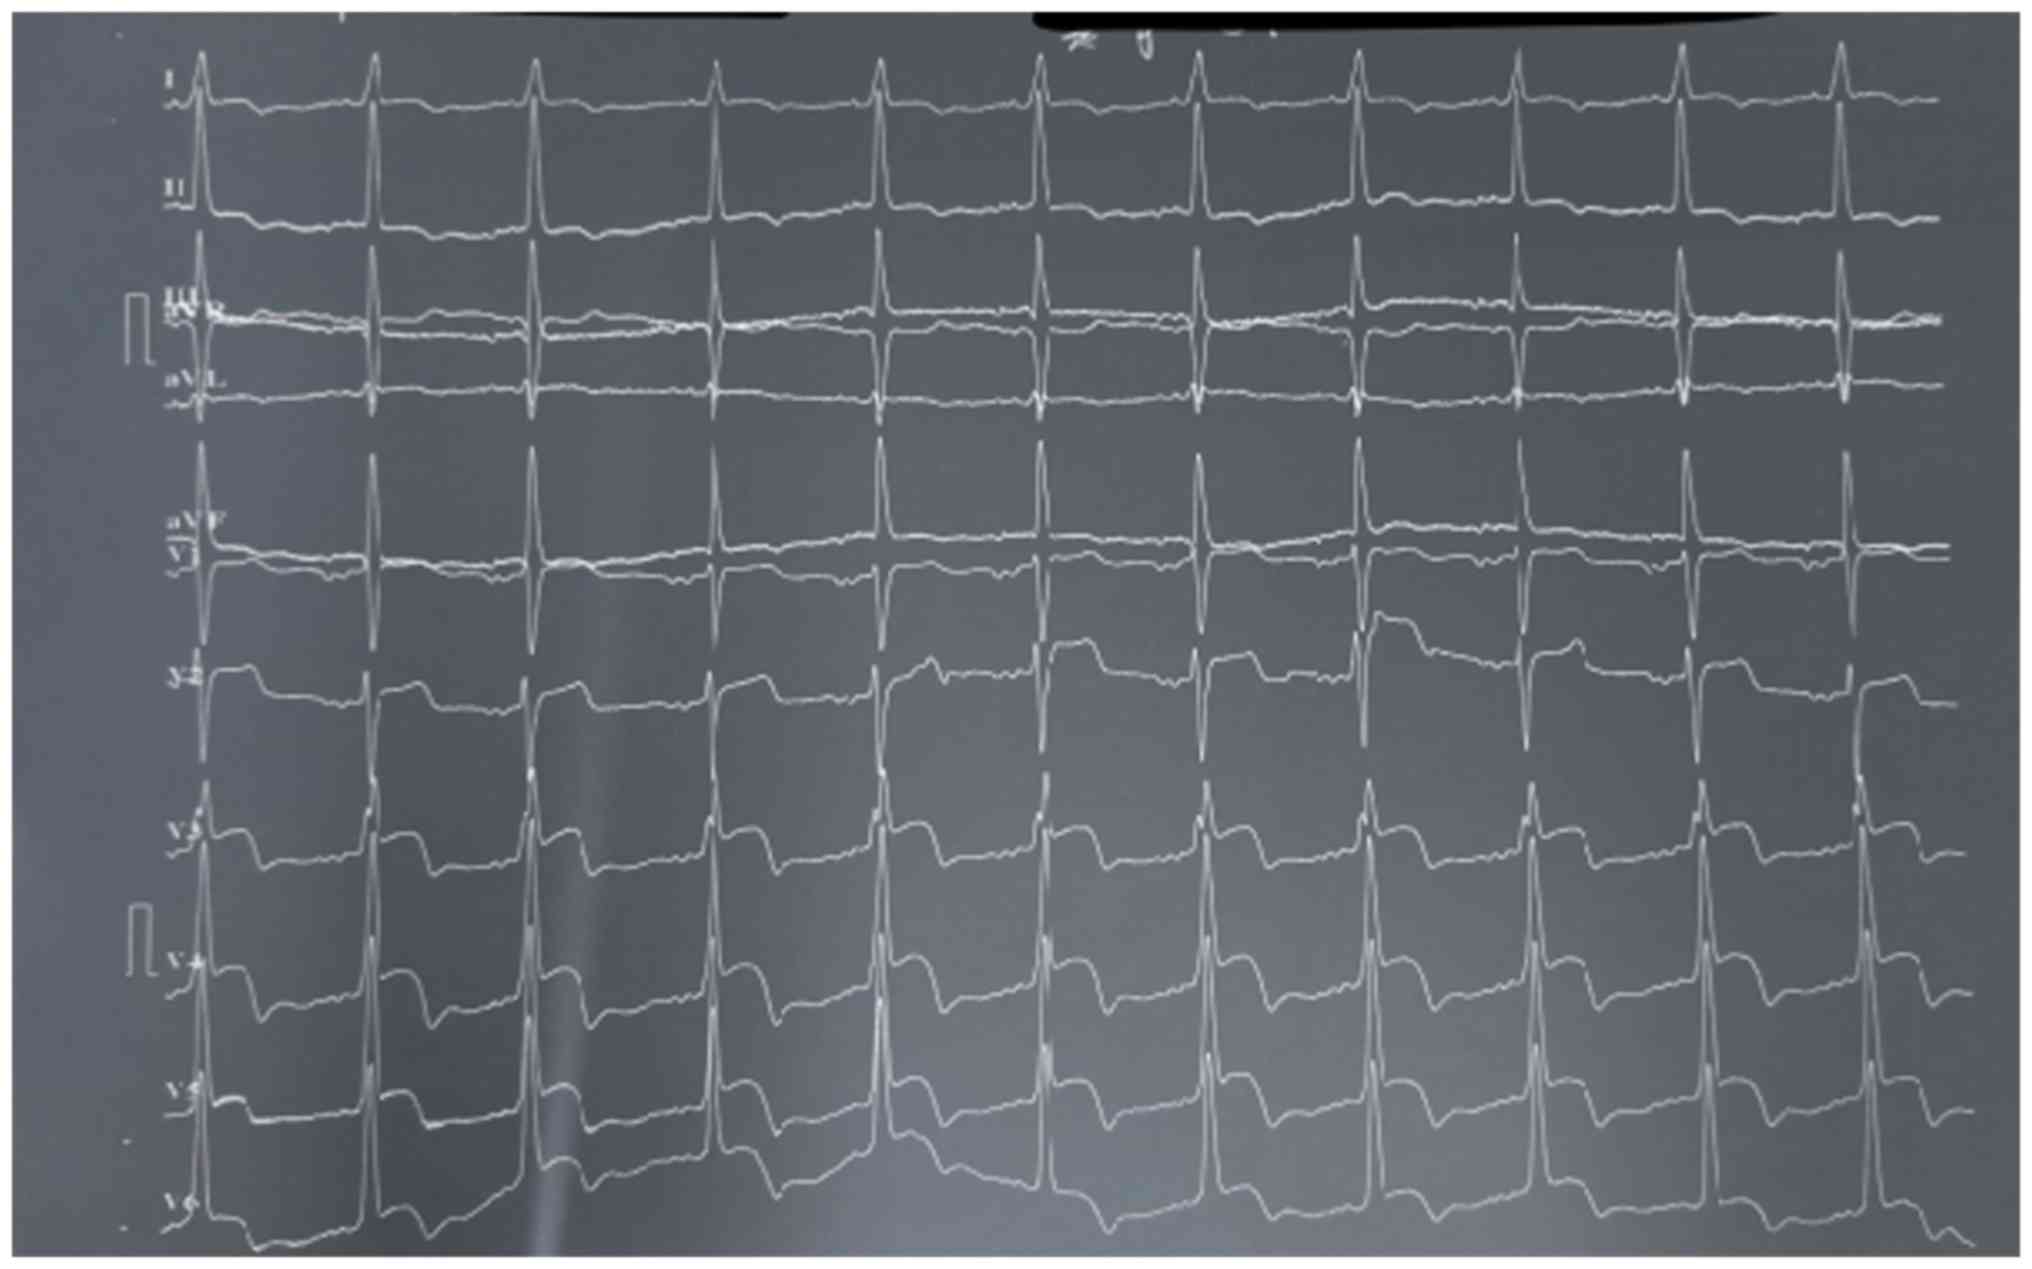

A 61-year-old Chinese male was admitted to his local cardiology department in June 2016 due to episodes of syncope after palpitation at rest. The patient had no family history of heart disease and his electrocardiogram indicated monomorphic ventricular tachycardia (Fig. 1). The initial troponin I level was 42.96 ng/ml and the patient was diagnosed with ST-segment elevation myocardial infarction. The abnormal electrocardiogram prompted invasive coronary angiography, which provided no evidence of obstructive coronary artery disease. The electrocardiogram that was then performed exhibited sinus rhythm, ST elevation and T wave abnormality (Fig. 2). The sinus rhythm was quickly restored but could not be maintained.

Figure 1.

Twelve-lead electrocardiogram on 19th June 2016 indicating sustained monomorphic ventricular tachycardia.

One year later, the patient experienced an electrical storm with 100 episodes of sustained ventricular tachycardia (VT) and multiple ICD shock (Fig. 6). Recurrent sustained monomorphic VT was terminated by increased doses of amiodarone and β-blocker. Furthermore, the patient experienced dyspnea on exertion. On transthoracic echocardiography, an apical aneurysm and a provoked mid-ventricular gradient of 64 mmHg were noted. The patient refused surgical treatment and but provided written informed consent to undergo alcohol septal ablation. Hemodynamic assessment revealed a significant intra-ventricular pressure gradient of 69 mmHg (LV apex, 169 mmHg; LV outflow, 100 mmHg; Fig. 7A). Repeated hemodynamic measurements after the procedure revealed a decrease of the post-extrasystolic gradient to 37 mmHg (LV apex, 135 mmHg; LV outflow, 98 mmHg) at the mid-ventricular level (Fig. 7B). The fourth and the fifth septal branches were dominant and echocontrast injection into target vessels resulted in the largest echocontrast view in the hypertrophic muscle segment. Therefore, the fourth and the fifth septal branches were assumed as target vessels and occlusion of these vessels resulted in a significant decrease in the intraventricular pressure gradient. The post-procedural echocardiographic examination indicated reductions in the left atrial dimension to 30 mm, intra-ventricular septum thickness to 20 mm and a mid-ventricular peak systolic gradient of 19 mmHg. There were no further VT episodes during treatment with amiodarone (200 mg, once a day) and metoprolol (47.5 mg, twice per day).

Figure 6.

Twelve-lead electrocardiogram on 20th July 2017 indicating short-burst anti-tachycardia pacing followed by ventricular tachycardia.